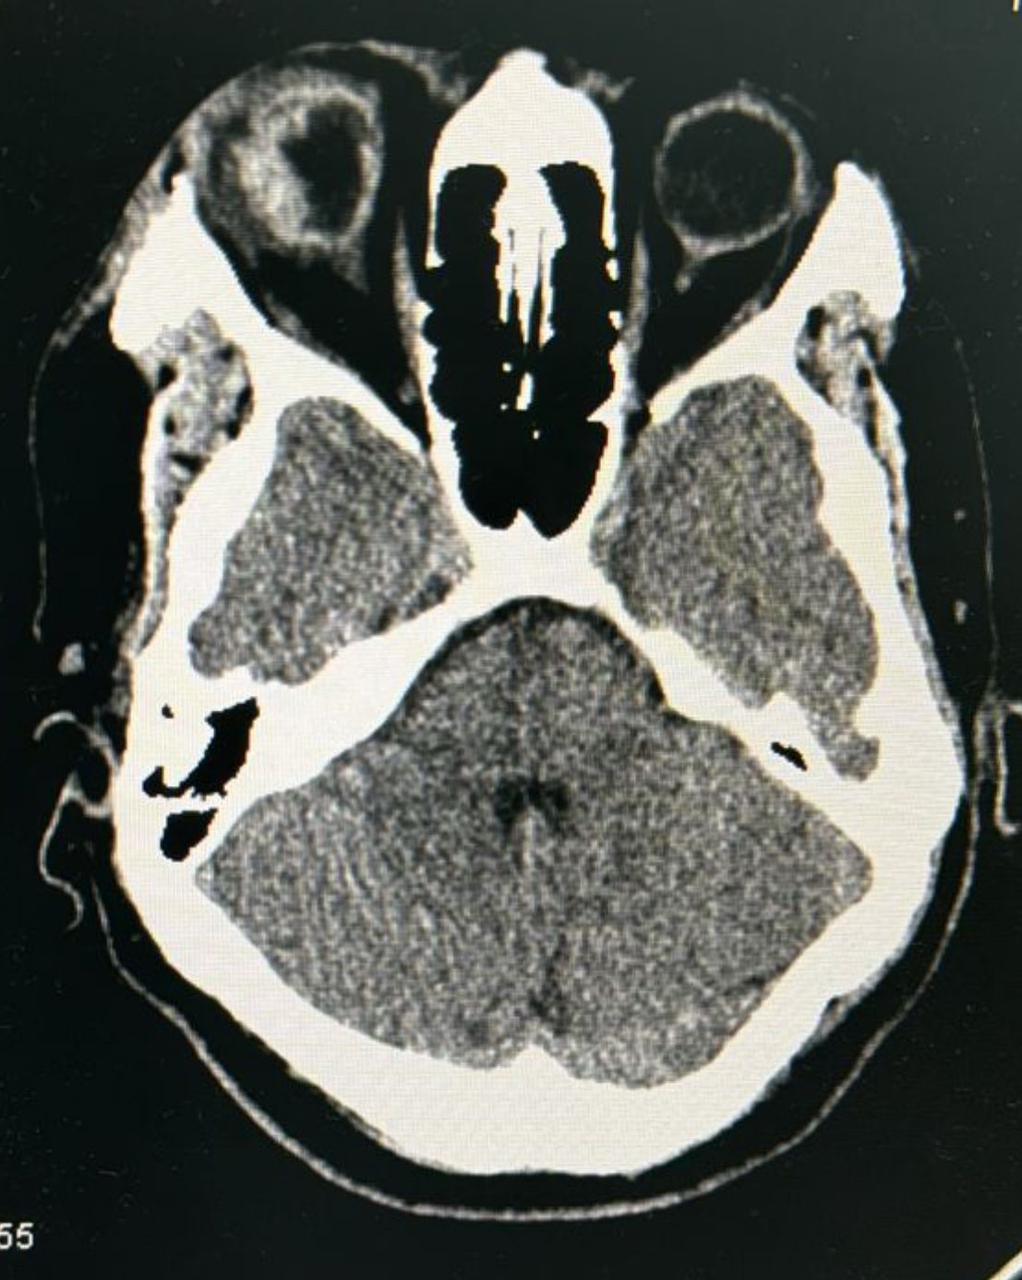

فور وصول المريض لطوارئ المستشفى إجريت له الأشعة المقطعية والفحوصات الأساسية السريعة بإشراف الطبيبة المناوبة الدكتورة: زهراء الغانم حيث بدأت مع المريض العلاج قبل ان يتم التواصل مع رئيس قسم العيون بشبكة القطيف الصحية إستشاري جراحة الشبكية والماء الأبيض الدكتور طه مصطفى سنبل الذي أجرى عملية صعبة فتح من خلالها ملتحمة العين ليكتشف شق كبير يمتد لخلف العضلة المستقيمة الإنسية،